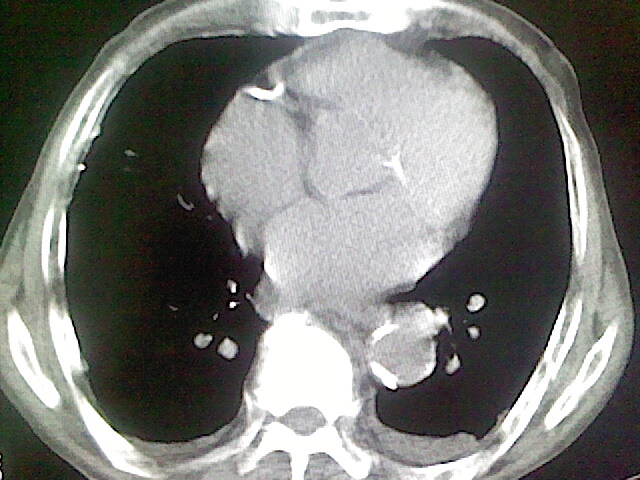

以下是引用zsl6918在2008-8-28 16:49:00的发言:[br]双肺炎性病灶,食管狭窄估计与心房增大压迫所致。

以下是引用xulianj在2008-8-28 20:36:00的发言:[br]慢支肺气肿伴感染,右上肺陈旧性结核;食道建议胃镜检查。

以下是引用wqs571018在2008-8-28 21:18:00的发言:[br]慢支继发感染,右上肺陈旧性结核;食道建议胃镜检查。